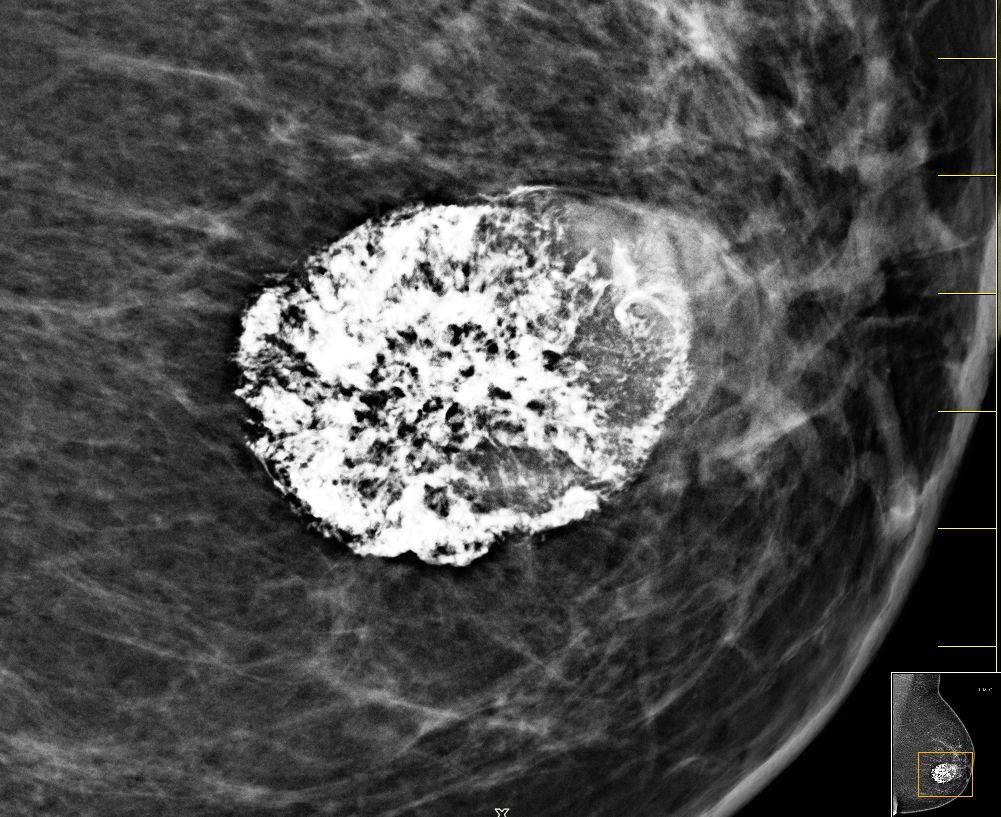

| Fall | 72-jährige Frau, bei der vor 5 Jahren ein gutartiger Tumor diagnostiziert wurde. Vor 8 Monaten war der Tumor auf 4cm angewachsen. Die Exzision wurde empfohlen. Jetzt war der Tumor 66 mm groß, sehr hart und teilweise verkalkt. | |||

Vergrößerung.![]() | ||